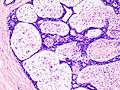

Histopathologic image of breast fibroadenoma showing proliferation of intralobular stroma compressing and distorting the epithelium. H&E stain.